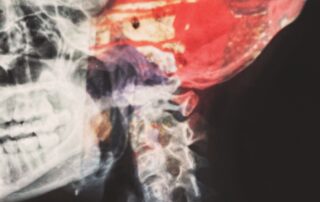

How To Calculate The Value Of A Brain Injury Settlement

By blog@attorney.example2.studiosight.com|2022-01-20T08:42:20+00:00January 19th, 2022|Categories: Uncategorized|Tags: best personal injury lawyer in california, brain injury, Brain injury attorney, brain injury attorney in California, brain injury attorney in Los Angeles, brain injury claim, brain injury law firm, brain injury lawyer, brain injury lawyer in California, brain injury lawyer in Los Angeles, Personal injury, Personal injury attorney, personal injury attorney in California, personal injury attorney in Los Angeles, Personal injury claim, personal injury claim in California, personal injury law firm, Personal injury law firm in california, traumatic brain injury|Comments Off on How To Calculate The Value Of A Brain Injury Settlement

Given the nature of traumatic brain injury, it is no [...]